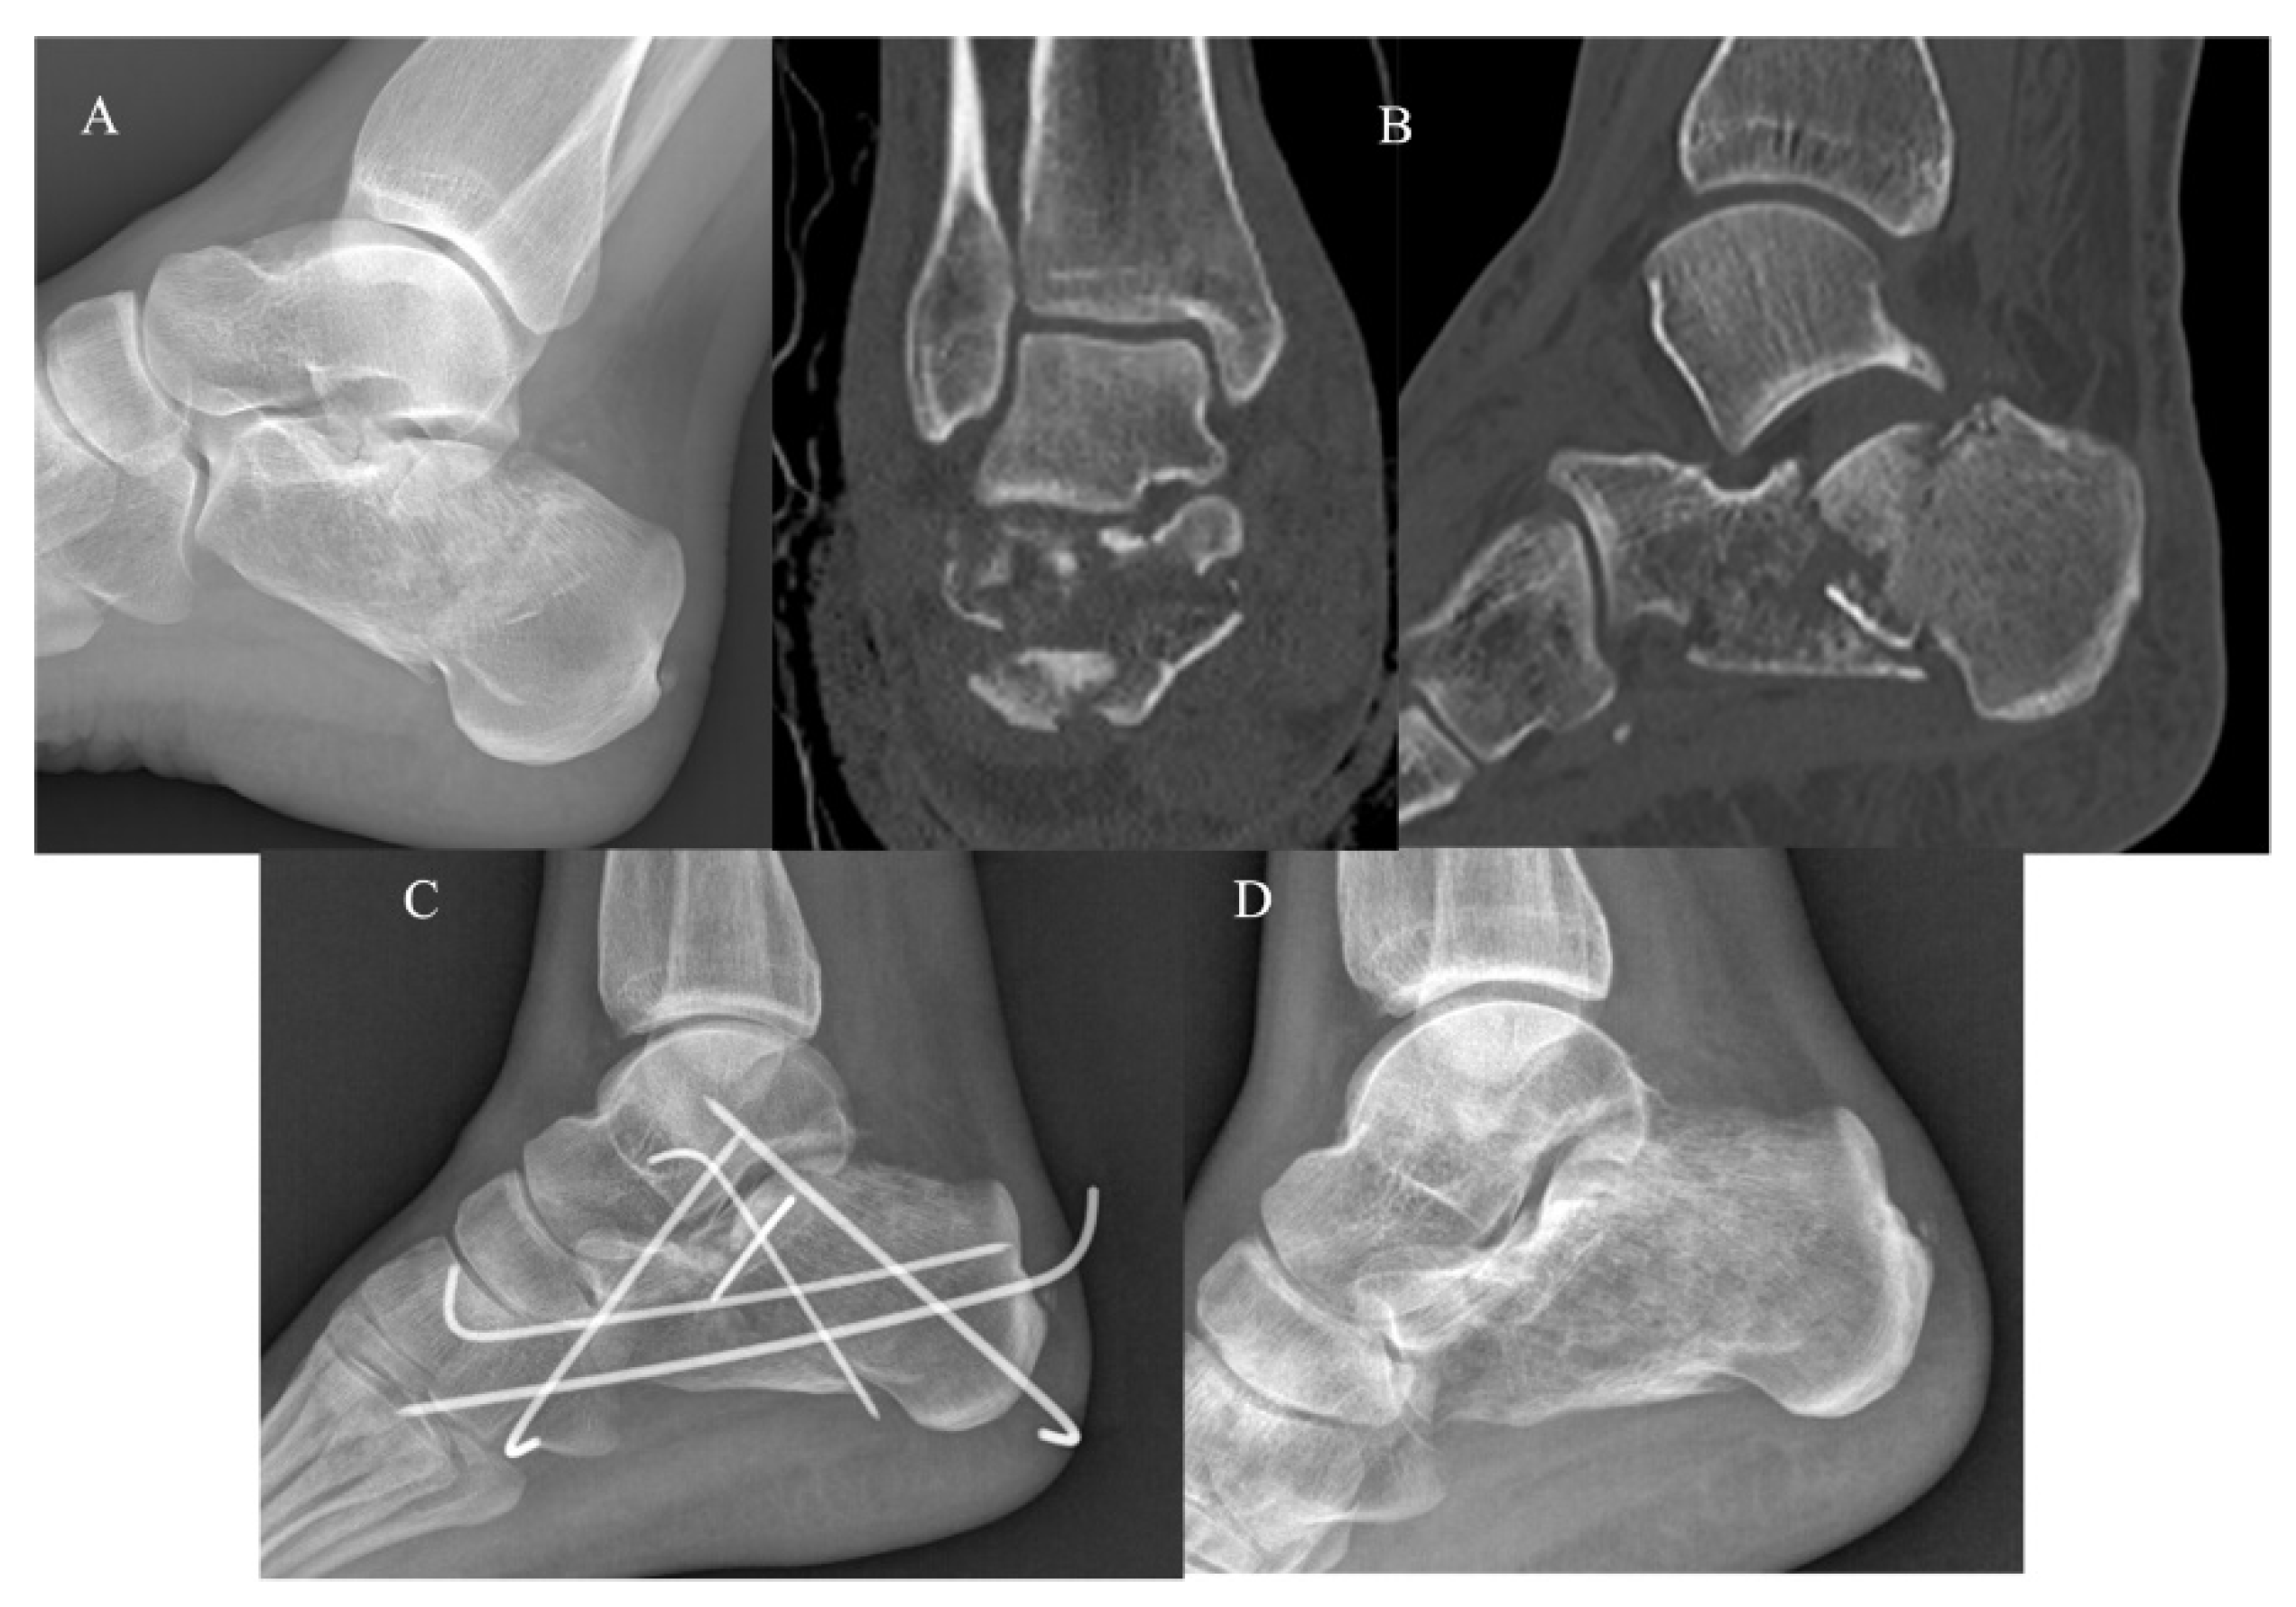

The KG (Figure 2) and PG (Figure 3) consisted of 20 and 22 CF, respectively. The group demographic characteristics and specific mean final follow-up are summarized in Table 1.

Figure 2.

Mini-open approach and K-wire fixation. (A) Pre-operative radiographs; (B) pre-operative CT scan in coronal and sagittal plane showing a Sanders III CF; (C) post-operative radiograph control; (D) post-operative radiographs at 4-year follow-up.